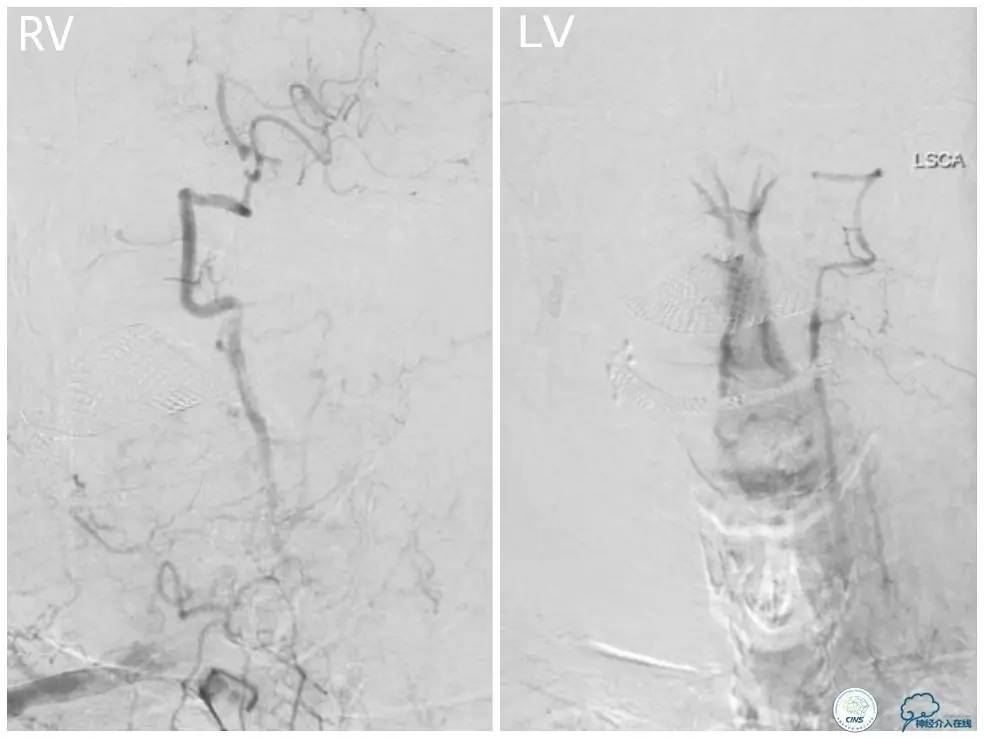

外院DSA(图3):右椎动脉起始处显示不清,右椎动脉V4段重度狭窄,左椎动脉V2-3段经侧支代偿显影。

图3